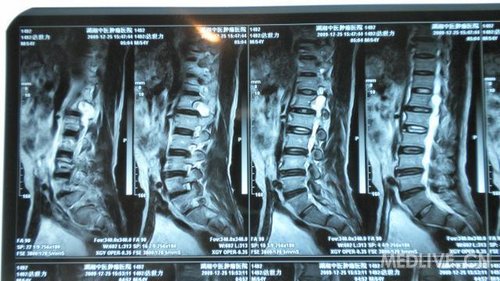

串者因腰椎间盘突出入院治疗,但询问病史查体时发现患者近1月来出现右腹股沟处麻木,局部感觉减退。做MRI等检查发现L1、2处椎管肿瘤。准备行手术治疗,但患者经济困难。各位专家指点一下选什么手术入路对脊柱稳定性影响比较小,尽量不上内固守。

X光片

还有MRI片

还有MRI片.